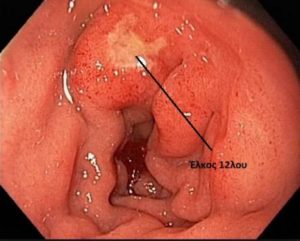

Ο γιατρός υποψιάζεται και προσανατολίζεται στην διάγνωση του έλκους βασιζόμενος στις πληροφορίες που παίρνει από το ιστορικό και την κλινική εξέταση του ασθενούς. Όπως όμως και για το έλκος του στομάχου η τελική διάγνωση τίθεται κατά την διάρκεια της γαστροσκόπησης.

Φωτο. Έλκος 12λου (λευκωπή περιοχή) όπως φαίνεται στην γαστροσκόπηση.